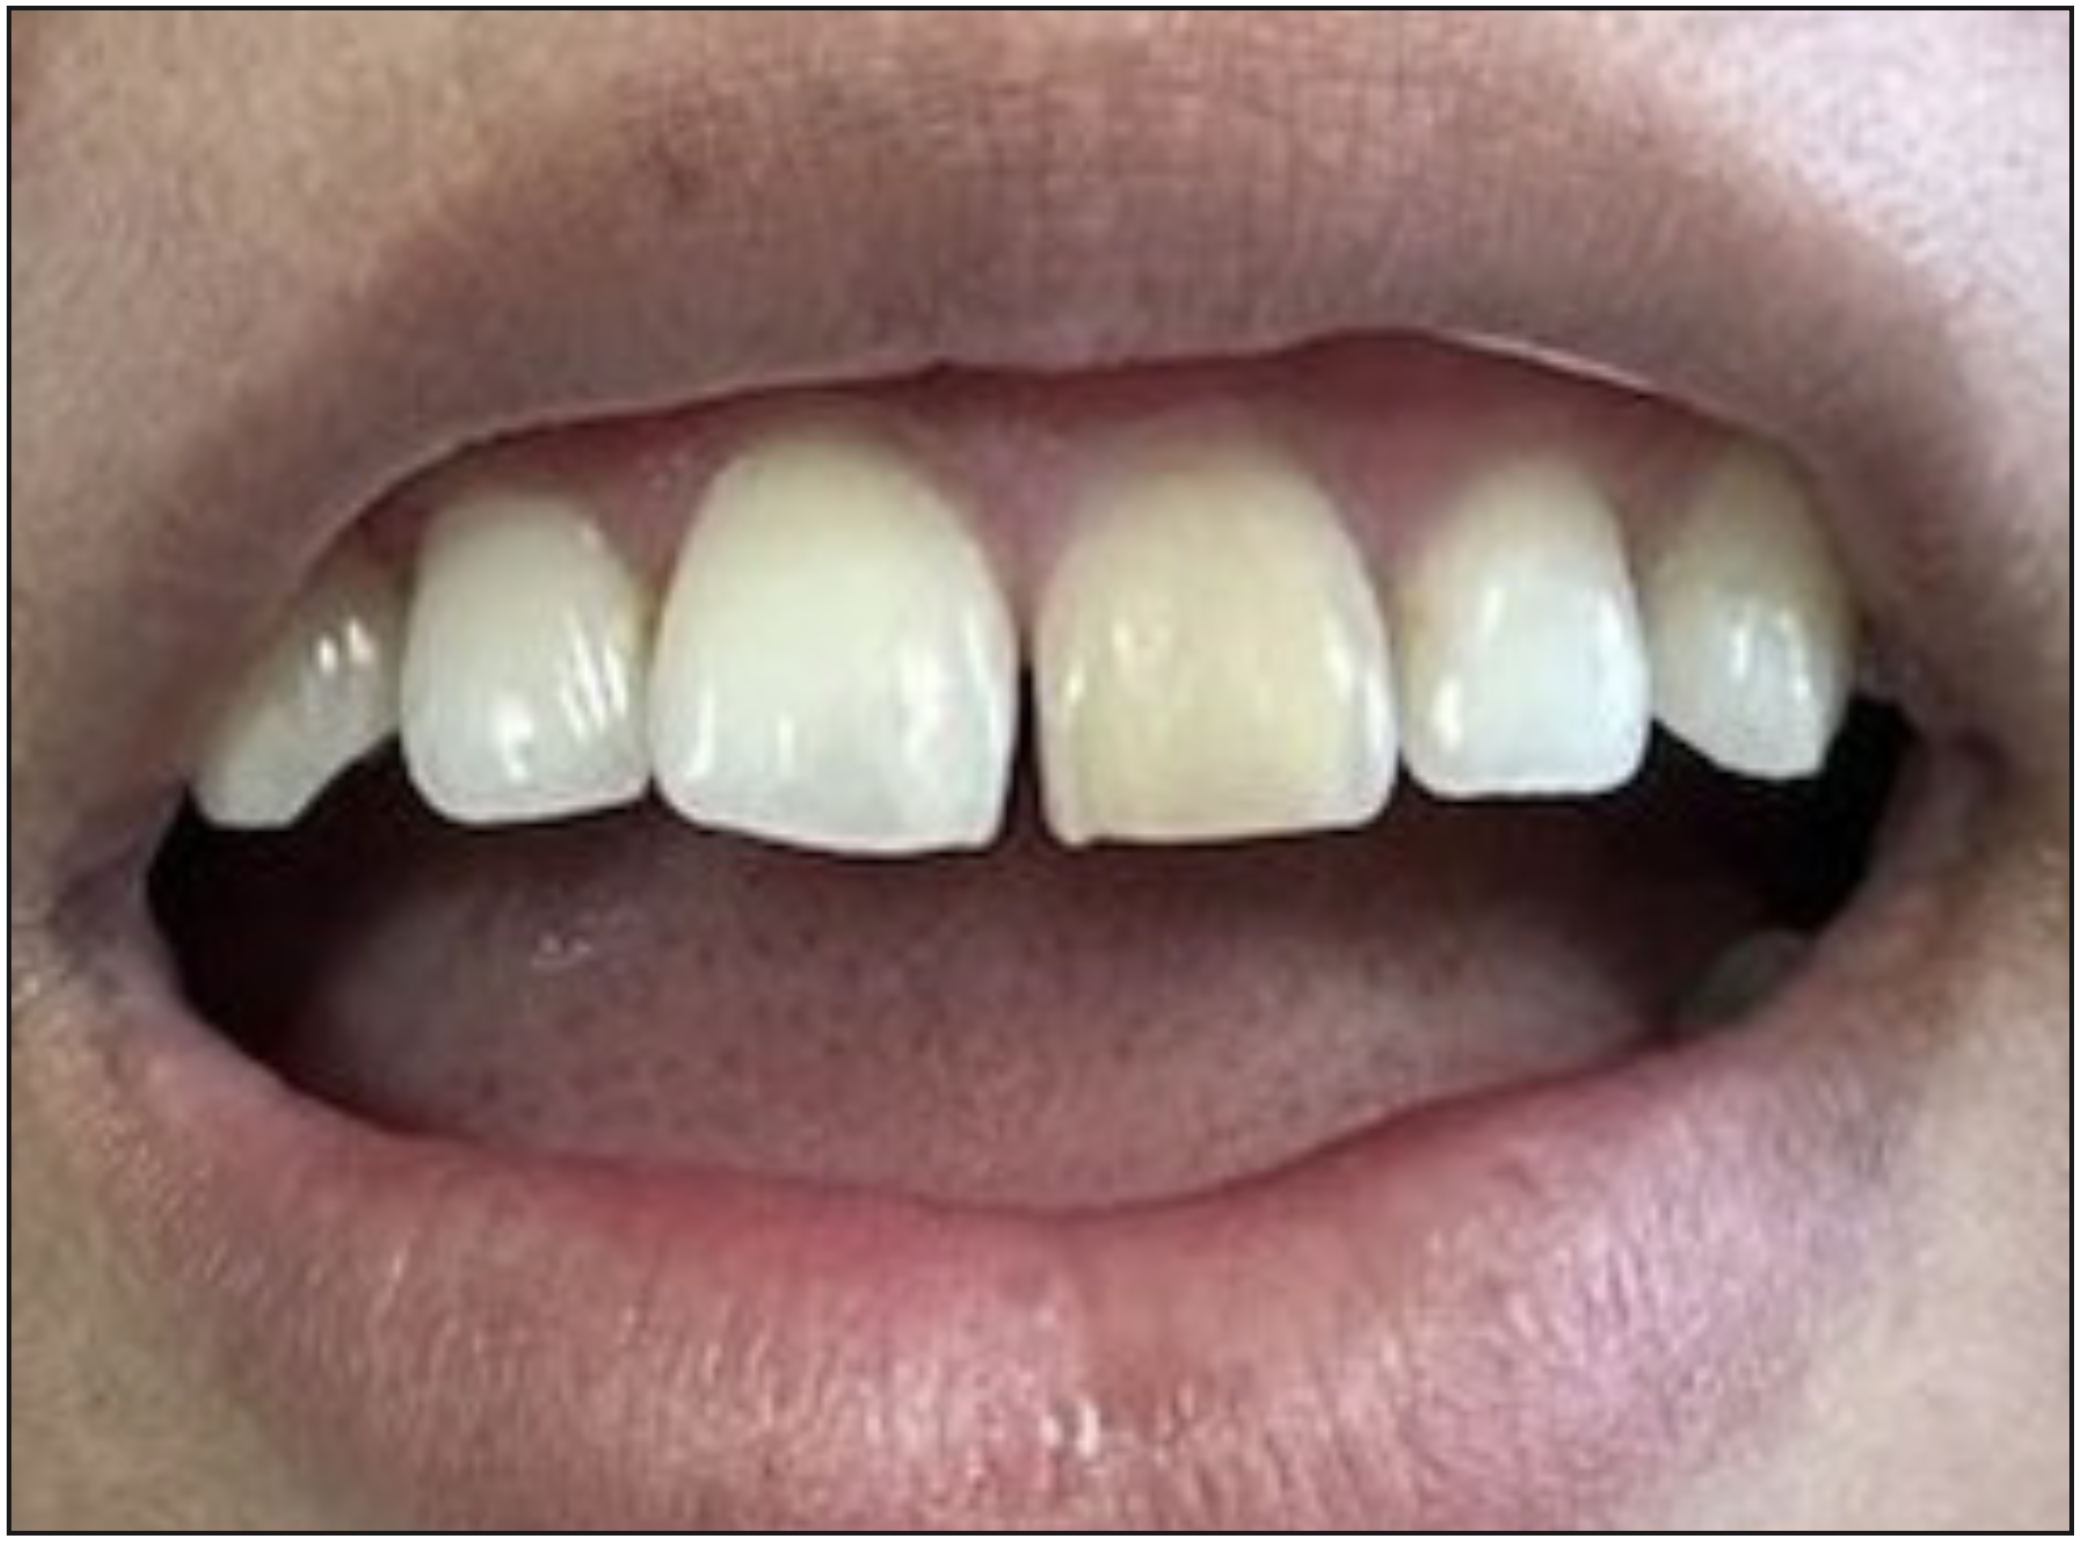

Paciente derivada a clínica para tratamiento de diente 2.1, debido a cambio de coloración en la corona del diente (Figura 1), ASA 1, relata trauma en ese diente hace varios años atrás, además presenta una lesión de caries cavitada en dentina por palatino.

Figura 1. Fotografía diente 2.1 con cambio de coloración dentaria.